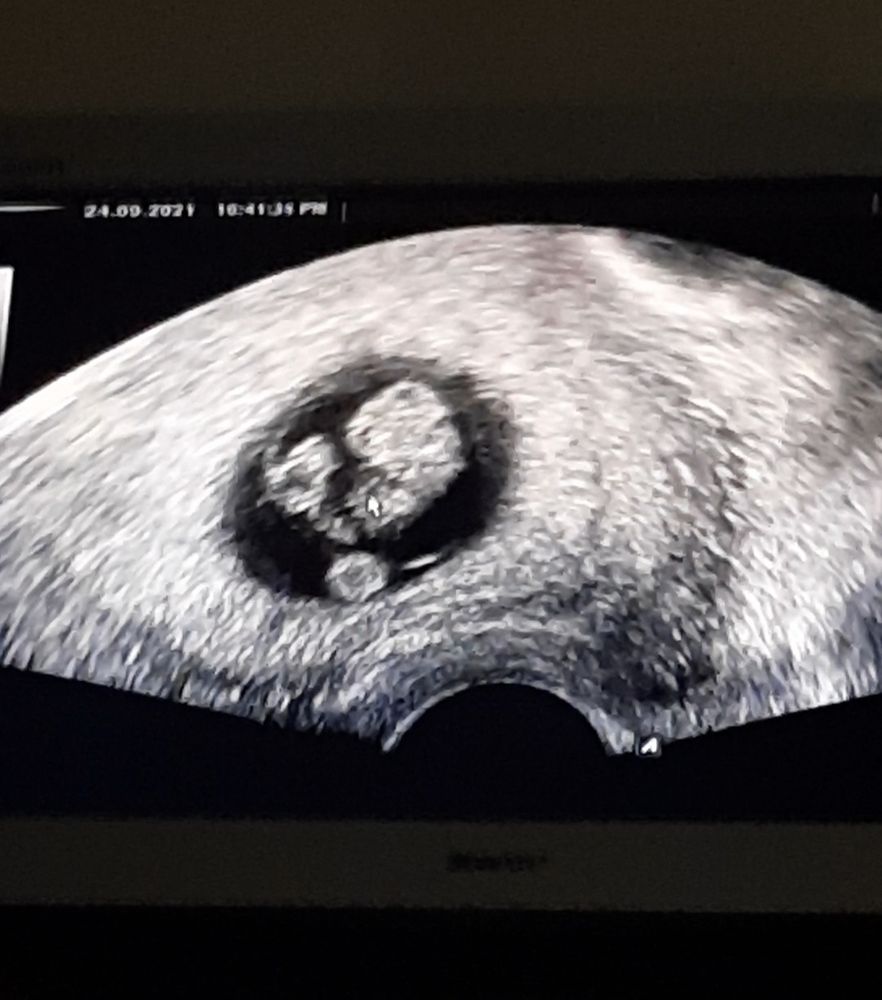

Это же пуповина?

Пуповинка)

Мила, вот я не знаю как оно должно быть. Двойня это же разные ПЯ? А тут какбы в одном, то есть близнецы? Это максимально неожиданно 😅 но я все таки думаю что пуповина так намоталась, но может девочки з близнецамм подскажут, опыта то больше.

Мила, да, там была масенькая точка бела и круглый жмя. Плодное яйцо четко было видно в матке, без сомнений. Но это точно не двойня. Либо близнецы либо все таки пуповина такая шальная 😅 я тоже тут читала сколько что и с первого раза фиг получиться, и нужно тесты мочить послк задержки и то не факт что увидишь, и на узи первое в 7-8 недель топать. А у нас первый цикл и все куда нужно, токсикоз на 10 дпо и вот как прилетели с отпуска, сделада тесты и реально охренела. Беременная полоска быстрее вылезла чем тестовая. Вообщем все не так как у всех 😅

Алена Ро, спасибо 🙏 может на неделе все таки переделаю узи, а то совсем не по себе. Муж уже успел ввпить вечерком сам с собой 😅😅😅 он постоянно говорил что было бы круто 2е. Но слова одно, а когда там 2 пульсации это уже ссыкотно 🤣